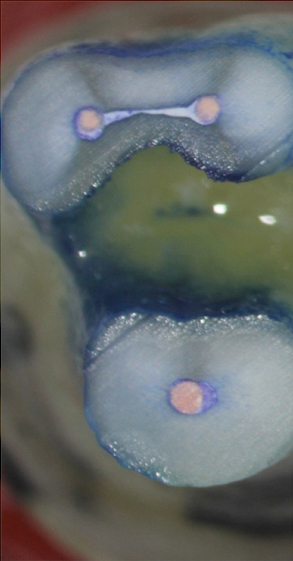

Fig 17. Retropreps and isthus filled. Courtesy of Dr. Sam Kratchman.

Figure 17

A patient presented with clinical symptoms and radiographic signs of post-endodontic disease (Figure 15). It was determined that the ledge on the mesial canals precluded retreatment and that an apicoectomy was to be performed. After locating the apicoectomy, it was possible to visualize both canals and an obvious isthmus between the two main canals (Figure 16). Retro-preparations were performed in the main canals, and the isthmus between them was grooved and the cavities filled with BC RRM-Putty (Figure 17). At the 20-month follow-up, the patient was asymptomatic and the radiograph showed complete healing (Figure 18).